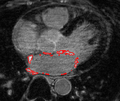

2013 Project Week:CARMA Scar Segmentation

Home < 2013 Project Week:CARMA Scar Segmentation